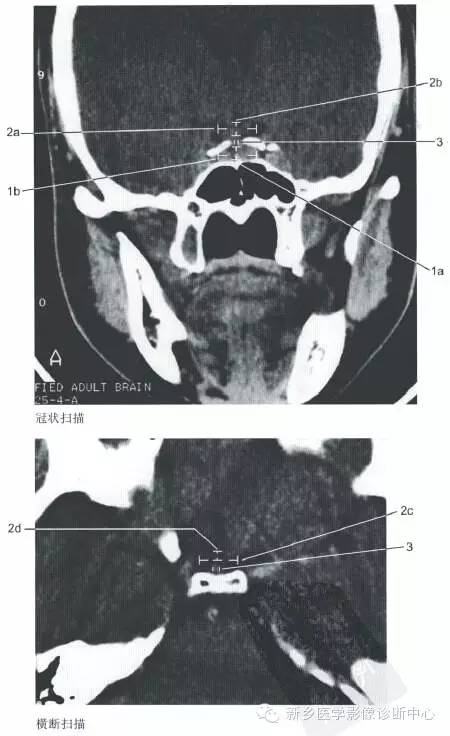

上一篇:眼眶的一些正常数据

下一篇:头部正常影像数据